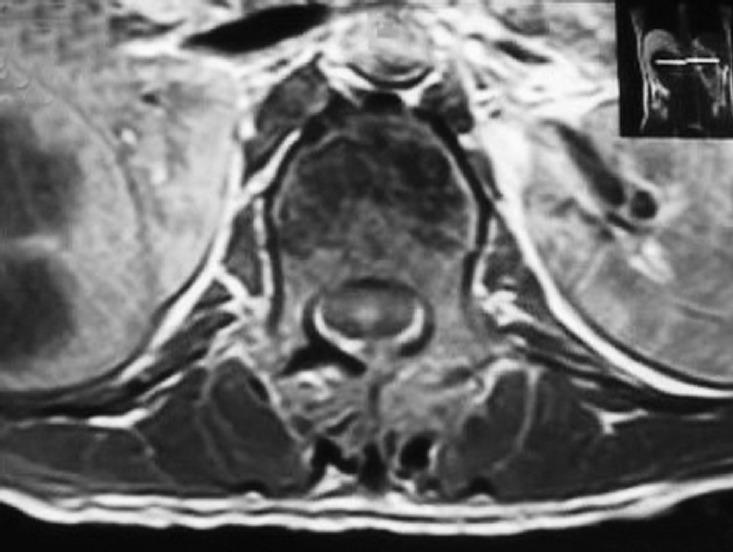

Patients who sustained injuries from T1 to L3 and required posterior surgery were prospectively studied. The treating surgeon and musculoskeletal radiologist participating in the study reviewed preoperative MRI images to characterize the level(s) of injury and the integrity of the six components of the PLC. These were classified as intact, incompletely disrupted, or disrupted. During the surgical procedure, the surgeon also classified each component of the PLC, and the radiologist's and surgeon's findings were compared.

对T1至L3受伤且需要进行后路手术的患者进行前瞻性研究。参与研究的主治外科医生和肌肉骨骼放射科医生回顾术前MRI图像,以确定损伤水平和PLC六个组成部分的完整性。这些被分类为完整、不完全断裂或断裂。在手术过程中,外科医生也对PLC的每个组成部分进行分类,并比较放射科医生和外科医生的检查结果。